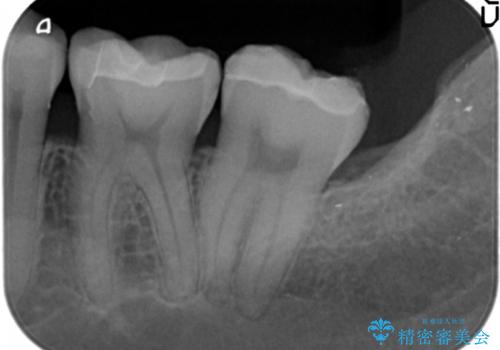

- 笑った時に見える下顎の銀歯を白くしたいと希望され来院されました。

銀歯を丁寧に外したのち、セラミックインレーによる修復を計画します。